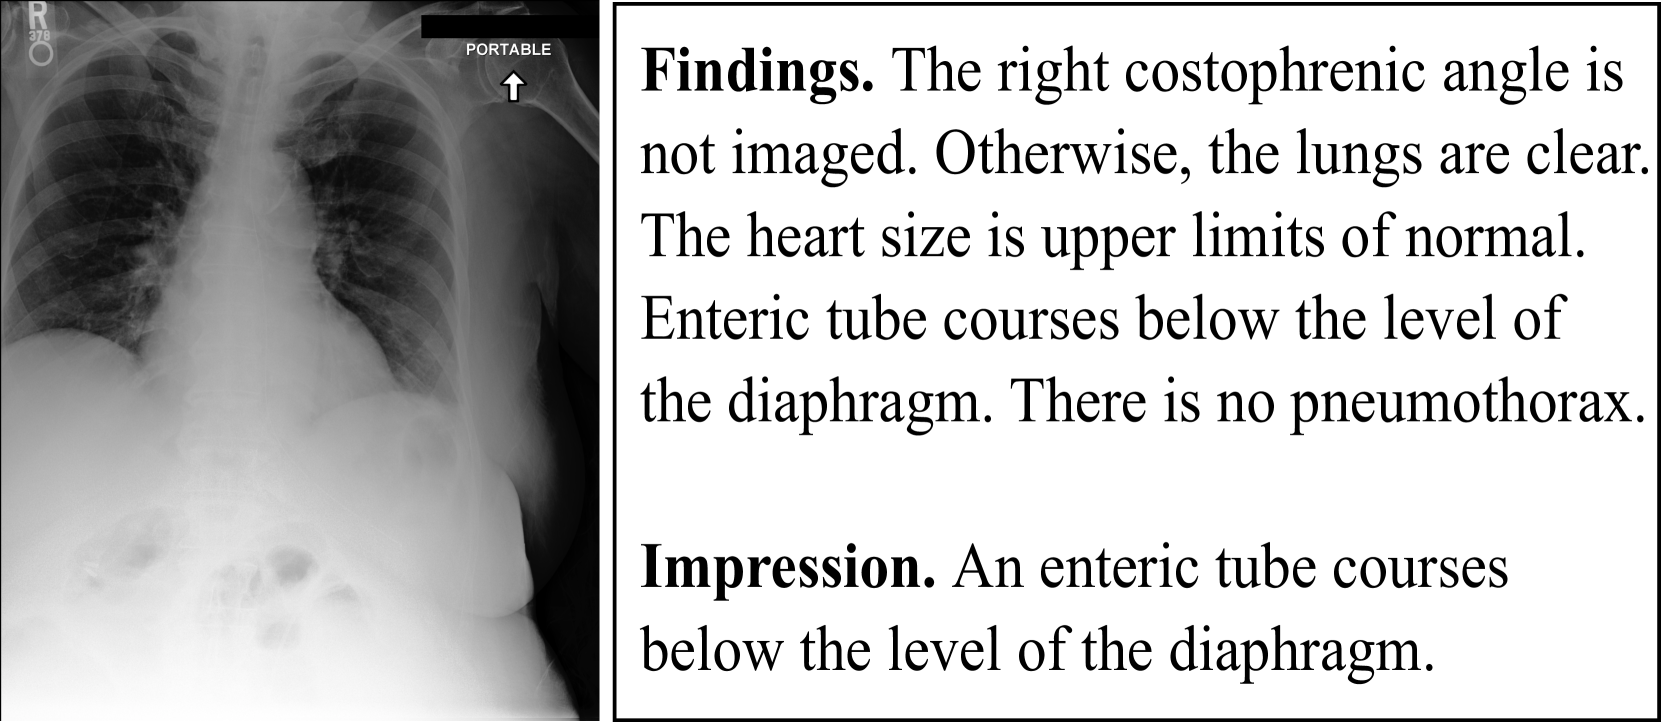

Figure 3: An example of a radiography along with its corresponding medical report consisting of ‘findings’ and ‘impression’.

We evaluate slog on the Mimic-CXR-IV data set (Johnson et al., 2019), one of the largest publicly available medical decision data sets, consisting of 227,835227835227,835227 , 835 radiology reports and 377,110377110377,110377 , 110 chest X-ray scans. We focus on the findings and the impression sections of the reports. As shown in Fig. 3, the findings are text-based descriptions of what can be observed in the scan, and constitute the basis on top of which the expert forms their impression, i.e., their initial opinion about the potential pathologies of a patient. We discarded examples where either findings or impressions were not available, resulting in the training, validation and test splits presented in Table 1.